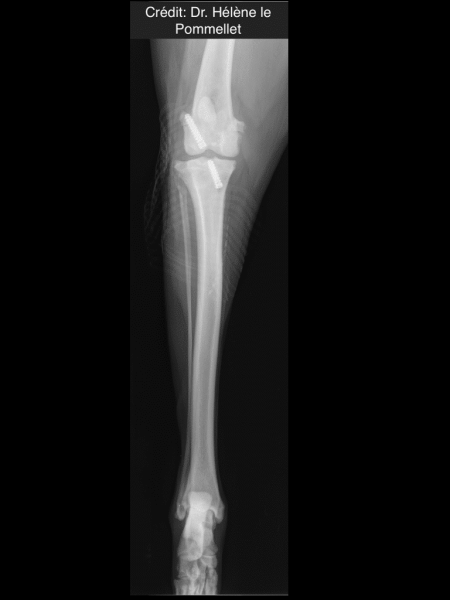

Radiologické snímky